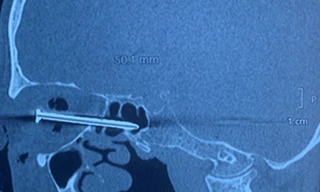

TPO - Bị hàng xóm dùng đũa tấn công, người đàn ông nhập viện trong tình trạng dị vật xuyên từ hốc mắt phải sang hốc mũi trái, nguy cơ thủng nhãn cầu. Ca phẫu thuật cứu bệnh nhân được các bác sĩ của Bệnh viện Mắt TPHCM và Bệnh viện Tai Mũi Họng khẩn trương thực hiện.